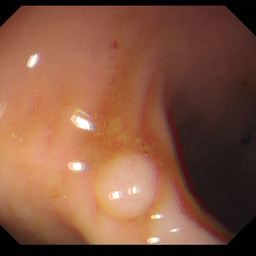

Medical image segmentation is a primary task in many applications, and the accuracy of the segmentation is a necessity. Recently, many deep learning networks derived from U-Net have been extensively used and have achieved notable results. To further improve and refine the performance of U-Net, parallel decoders along with mask prediction decoder have been carried out and have shown significant improvement with additional advantages. In our work, we utilize the advantages of using a combination of contour and distance map as regularizers. In turn, we propose a novel architecture Psi-Net with a single encoder and three parallel decoders, one decoder to learn the mask and other two to learn the auxiliary tasks of contour detection and distance map estimation. The learning of these auxiliary tasks helps in capturing the shape and boundary. We also propose a new joint loss function for the proposed architecture. The loss function consists of a weighted combination of Negative likelihood and Mean Square Error loss. We have used two publicly available datasets: 1) Origa dataset for the task of optic cup and disc segmentation and 2) Endovis segment dataset for the task of polyp segmentation to evaluate our model. We have conducted extensive experiments using our network to show our model gives better results in terms of segmentation, boundary and shape metrics.